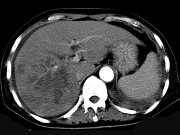

男,42岁,中上腹痛,轻度黄疸,结合CT图像,提出最可能的诊断 ( ) XH-26761.jpg XH-26762.jpg XH-26763.jpg

题型: 单选题 分类: 肿瘤放射治疗学

• A.肝脓肿

• B.肝多发性囊肿

• C.肝癌肝内转移伴门脉癌栓形成

• D.胆管细胞癌

• E.肝血管瘤